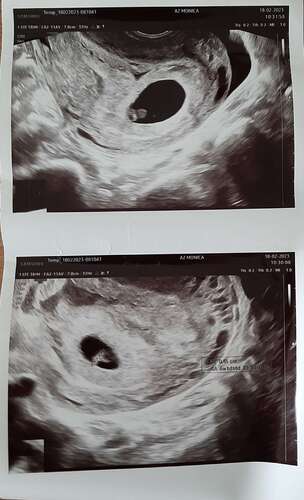

Ja hoor, en nu 21 weken zwanger. Niet te bang laten maken. Dit heet een hematoom en komt veel vaker voor dan je denkt.

Ja ik had mijn eerste echo gekregen vanwege bloedverlies met 5+3 en daar was toen een kloppend hartje te zien. Maar bij heel veel vrouwen lost dit vanzelf op😊